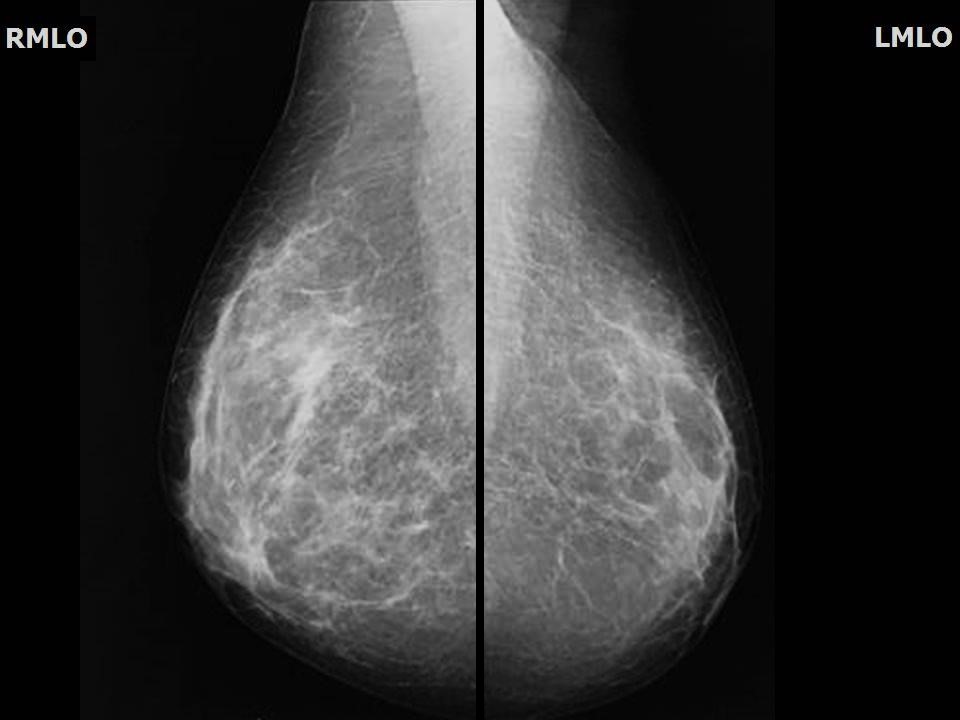

Что такое маммография: важность, процесс и результаты